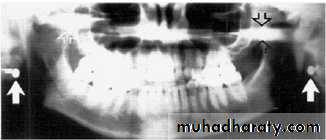

Stud earrings, real shadows (solid arrows)

with ghost shadows (open arrows).